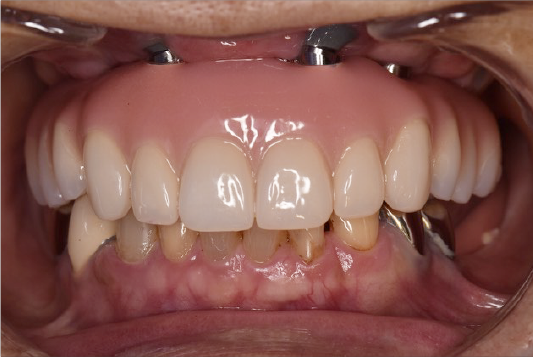

CASE01

■ 治療内容

上下顎All-on-4インプラント治療

■ 治療費用

7,438,000円(税込)

■ 治療期間

約10ヶ月

■ リスク

治療後の腫れや出血、またメンテナンスを怠ることで周囲炎のリスクあります。